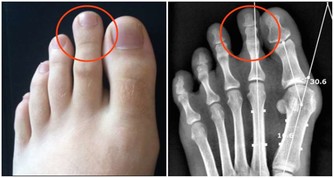

- 炎症與氧化壓力:某些情況下,過多的HDL可能失去其保護功能,反而引發炎症反應,加速動脈硬化進程。

- 與某些疾病的相關性:HDL過高可能與肝臟疾病、腎臟疾病或癌症風險增加有潛在關聯,但相關機制尚待進一步研究。